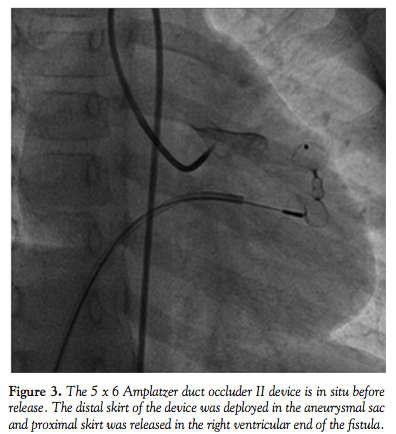

The procedure was done under caudal anesthesia and intravenous ketamine in the cardiac catheterization laboratory. After obtaining percutaneous femoral vessel access by Seldinger’s technique, 100 U/kg of heparin were administered prior to the procedure. Aortic root angiography and selective right and left coronary angiograms were done to delineate the artery feeding the fistula and its drainage (Figure 1). Angiogram showed a grossly dilated left coronary artery with an aneurysm and a fistula draining into the right ventricle. The left coronary artery and branches were poorly opacified, suggestive of coronary steal phenomenon. Through the 5 Fr cobra catheter, a 0.018˝ exchange-length wire (Terumo Corporation) was advanced into the left coronary artery. Through the fistulous track, the guidewire was negotiated into the right ventricle and then into the right atrium and superior vena cava. The tip of the wire in the superior vena cava was snared from the venous side using a 15 mm goose-neck snare.

An arterio-venous loop was made, and a 6 Fr shuttle delivery sheath (Cook Medical) was advanced over this wire from the venous end. However, the sheath could not be negotiated into the fistula from the right ventricular end (Figure 2). Hence, through the same delivery sheath, a 5 Fr right Judkin’s guiding catheter was introduced into the fistula. A 5 x 6 ADO II device was loaded and then advanced into the Judkin’s catheter and the distal skirt of the device was deployed in the aneurysmal part of the fistula.